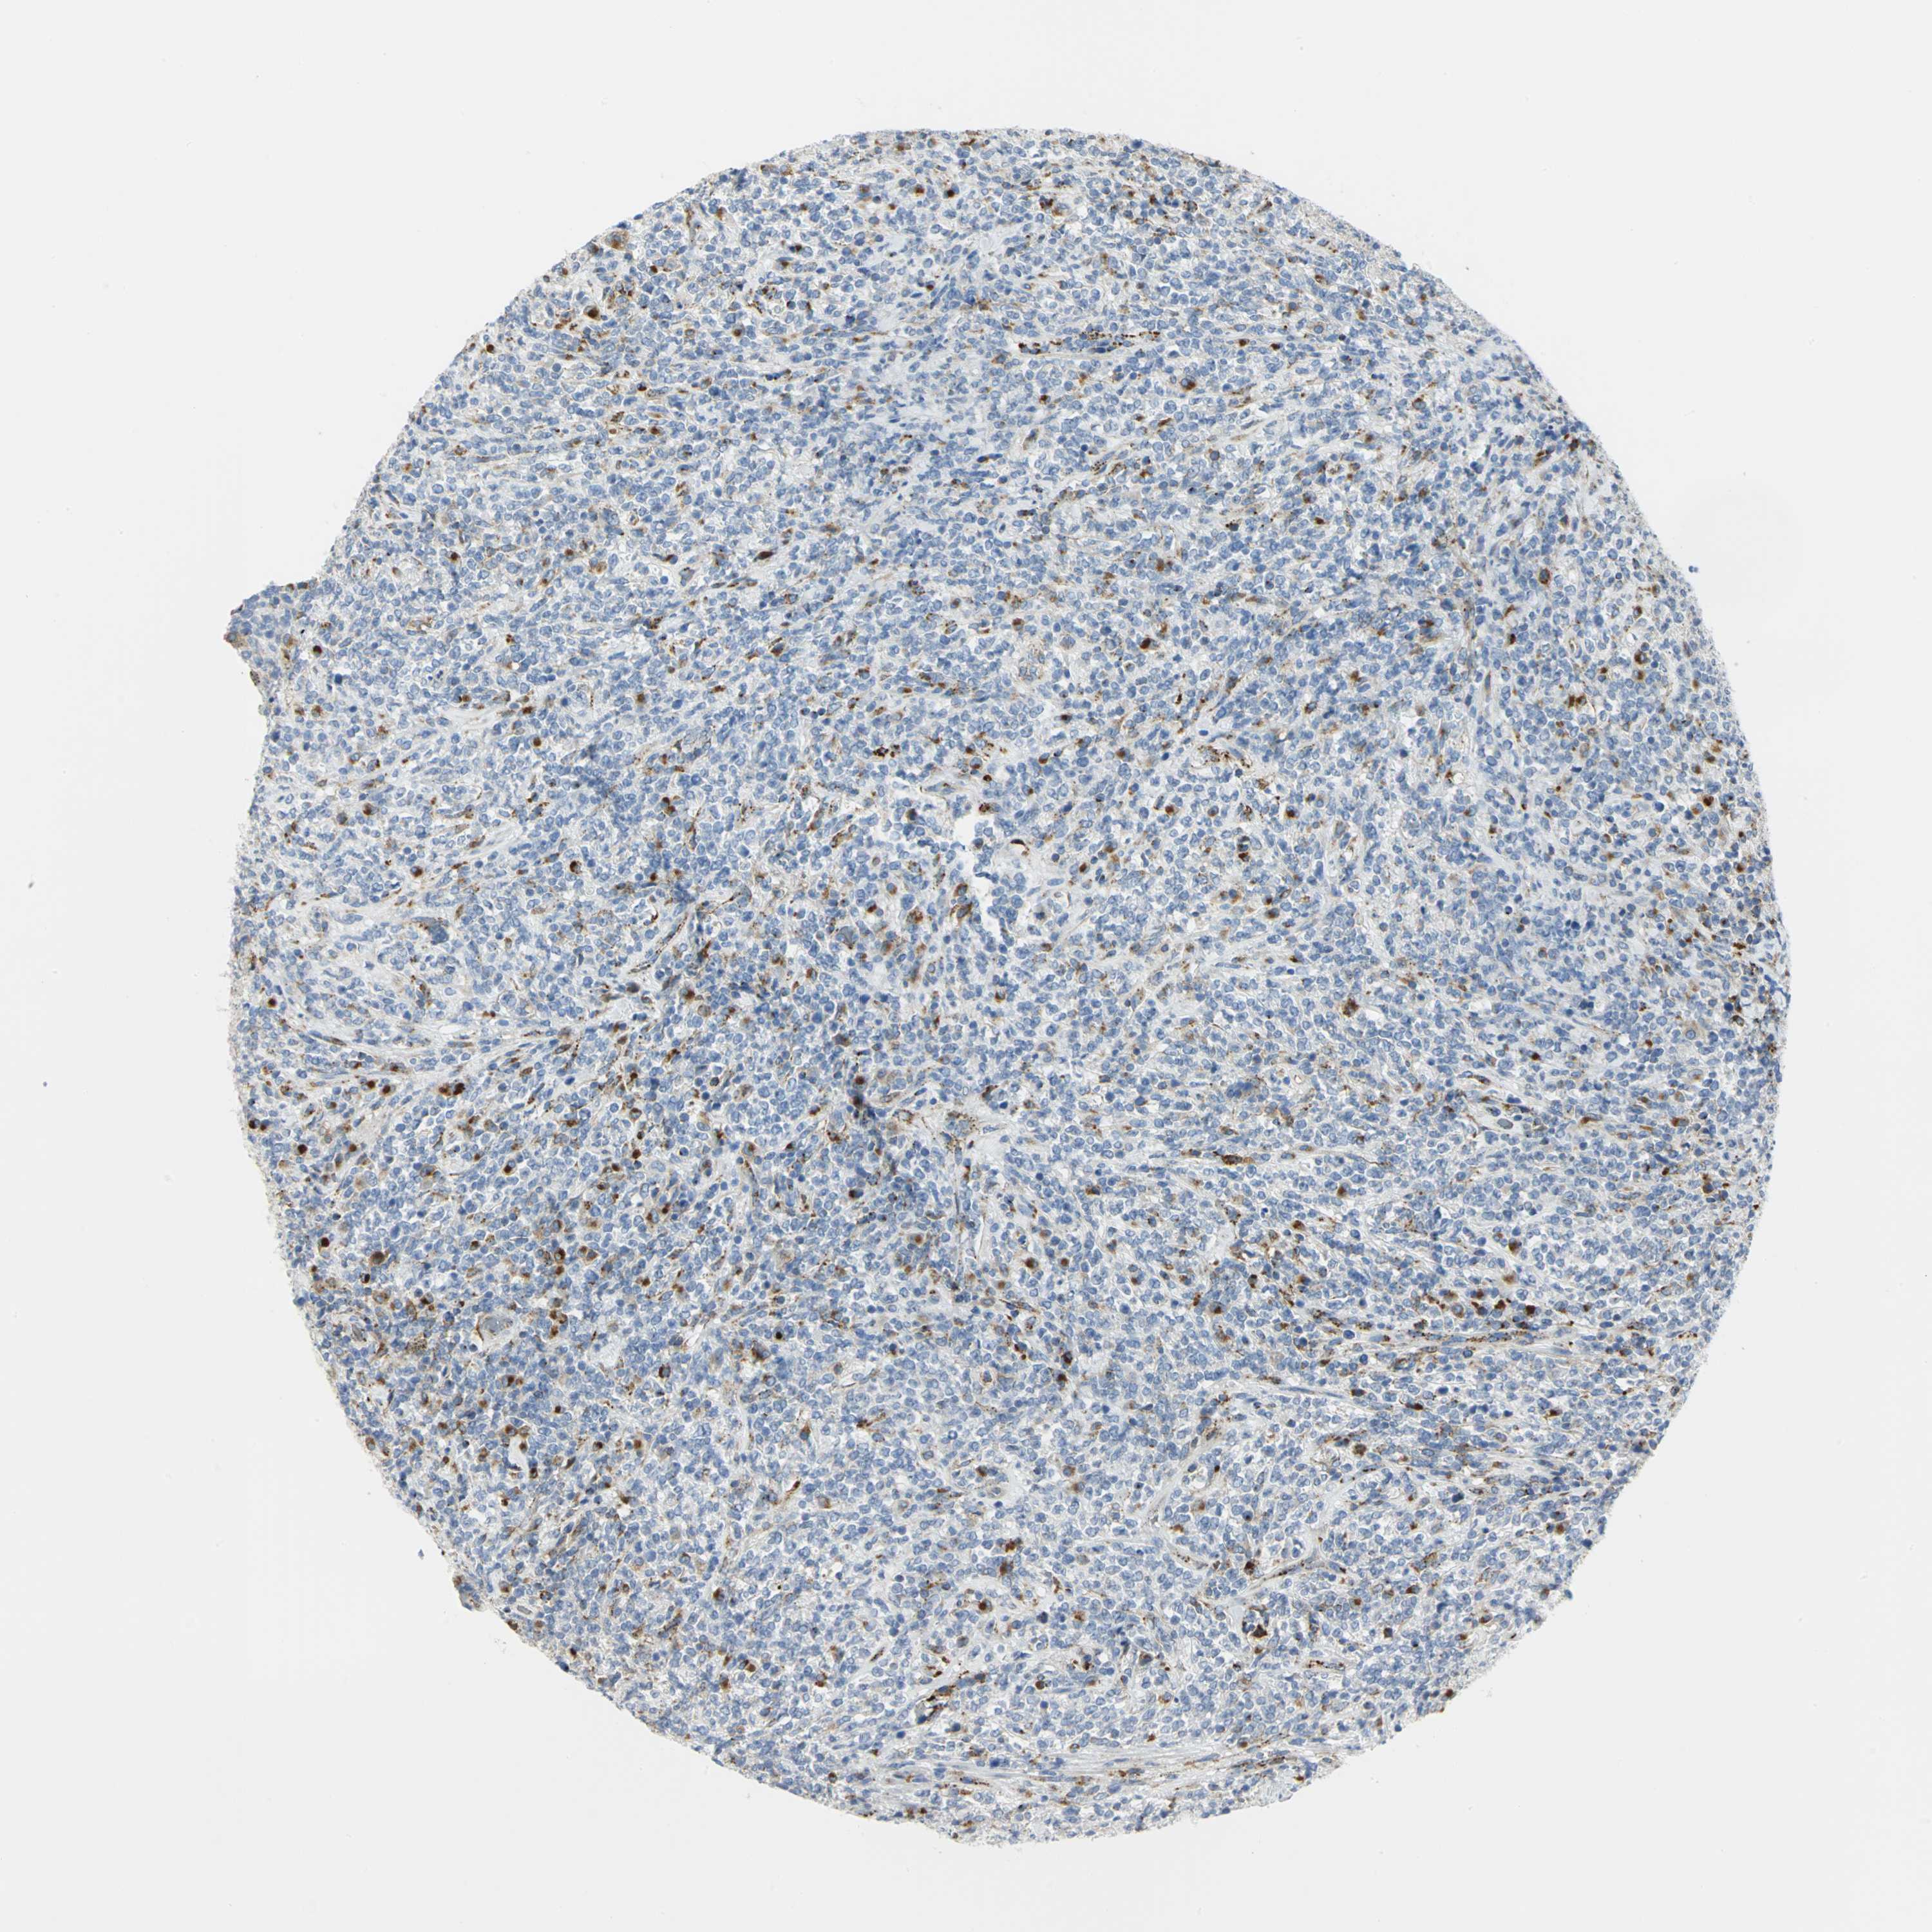

CANCER LYMPHOMA Show tissue menu

LYMPHOMA - Protein expressioni

A mouse-over function shows sample information and annotation data. Click on an image to view it in a full screen mode. Samples can be filtered based on level of antibody staining by selecting one or several of the following categories: high, medium, low and not detected. The assay and annotation is described here.

Antibody stainingi

Antibody staining in the annotated cell types in the current human tissue is reported as not detected, low, medium, or high, based on conventional immunohistochemistry profiling in selected tissues. This score is based on the combination of the staining intensity and fraction of stained cells.

Each image is clickable and will lead to virtual microscopy that enables deeper exploration of all samples and also displays staining intensity scores, fraction scores and subcellular localization as well as patient and tissue information for each sample.

Antibody HPA005554

Antibody CAB025183

Staining

High

Medium

Low

Not detected

Intensity

Strong

Moderate

Weak

Negative

Quantity

>75%

75%-25%

<25%

None

Location

Nuclear

Cytoplasmic/membranous

Cytoplasmic/membranous,nuclear

Hodgkin's disease, NOS

Malignant lymphoma, non-Hodgkin's type, High grade

Malignant lymphoma, non-Hodgkin's type, Low grade